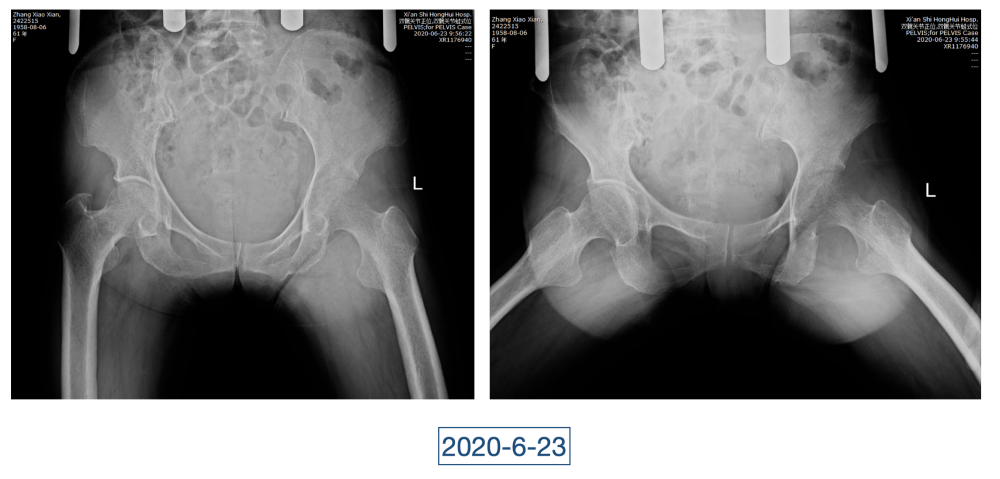

一直到了四月,因为髋关节疼痛的原因,她又来到红会医院关节病医院。李辉见到的黄大娘是坐着轮椅的,家里人说她已经到了卧床不起的地步,原本近107斤的人只用了3个月时间就瘦到了34斤。“这是患上了什么大病,才能让人变成这个样子?”看着憔悴不堪,可以用皮包骨头来形容的黄大娘,李辉心里一沉,担心起来。

全身上下11处骨关节被破坏!密密麻麻的诊断看得李辉毫无思绪,这么久都查不出来的病因能让他查出来吗?一时间,他也说不出话。看着黄大娘深深凹陷的双眼,浑身上下几乎看不见肉,就像罩着一层饥饿的青黄色的薄皮。过了好一会儿,他叹了口气,说:“先住下吧,用药把关节疼痛缓解一下,再想办法。”

经过科室讨论、会诊,李辉也查阅了很多资料,按照黄大娘的症状,他跟之前的接诊医生一样,觉得应该是骨关节感染。可之前的穿刺、培养各种检查也做过,为什么没有找到致病菌?李辉想,或许是检查中出现了问题,没有查对地方。于是他决定,在B超引导下骨穿刺,通过最新技术精准定位病灶,只有这样也许才能抓到真正的“罪犯”。

在黄大娘入院第四天,李辉将她推入检查室,结果很快出来了,为烟曲霉菌感染。这个结果验证了李辉的想法,也解释了此前抗感染药物为何一直不奏效。“找到元凶就好办了,对症用药就可以。真菌感染本来治疗时间就很长,骨科类感染灶治疗时间更长,用了5个月的时间,终于治好了。”

近日随访得知黄大娘身体好转,李辉脸上的笑容掩饰不住,他说,据查阅文献,11处感染灶,这是全世界感染灶最多的骨关节感染,但现在,这罕见、复杂的病已经被治愈。